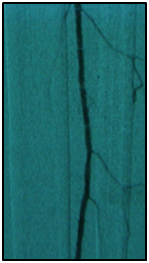

Final angiographic control showed patency of the fibular artery and dorsalis pedis, with direct flow for the first metatarsal artery, thus guaranteeing enough flow to heal the ulcer in six months after the procedure. In conclusion endovascular treatment has a high technical eligibility with good reported outcomes and represents an alternative for diabetics with CLI Disease (Figure 1 and 2).

• Figure 2 From left to right showing percutaneous transluminal BTK balloon angioplasty, and revascularization of the dorsalis pedis and plantar arteries by the fibular artery.